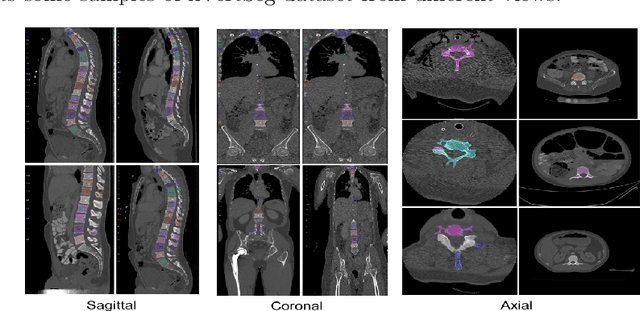

Abstract:Accurate segmentation of the vertebra is an important prerequisite in various medical applications (E.g. tele surgery) to assist surgeons. Following the successful development of deep neural networks, recent studies have focused on the essential rule of vertebral segmentation. Prior works contain a large number of parameters, and their segmentation is restricted to only one view. Inspired by DoubleU-Net, we propose a novel model named DoubleU-Net++ in which DensNet as feature extractor, special attention module from Convolutional Block Attention on Module (CBAM) and, Pyramid Squeeze Attention (PSA) module are employed to improve extracted features. We evaluate our proposed model on three different views (sagittal, coronal, and axial) of VerSe2020 and xVertSeg datasets. Compared with state-of-the-art studies, our architecture is trained faster and achieves higher precision, recall, and F1-score as evaluation (imporoved by 4-6%) and the result of above 94% for sagittal view and above 94% for both coronal view and above 93% axial view were gained for VerSe2020 dataset, respectively. Also, for xVertSeg dataset, we achieved precision, recall,and F1-score of above 97% for sagittal view, above 93% for coronal view ,and above 96% for axial view.